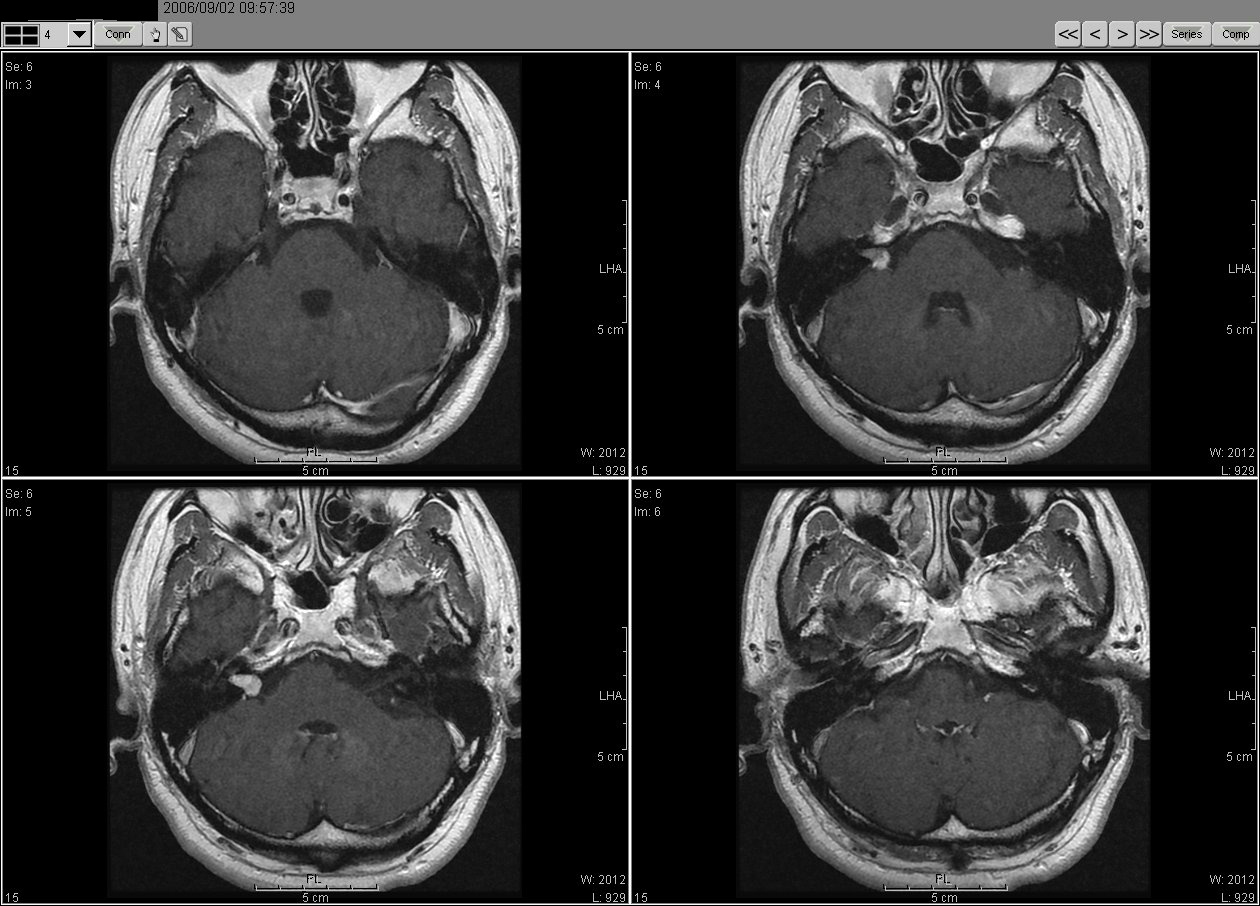

2006_09_02 MRI

2006_02_02MRI02